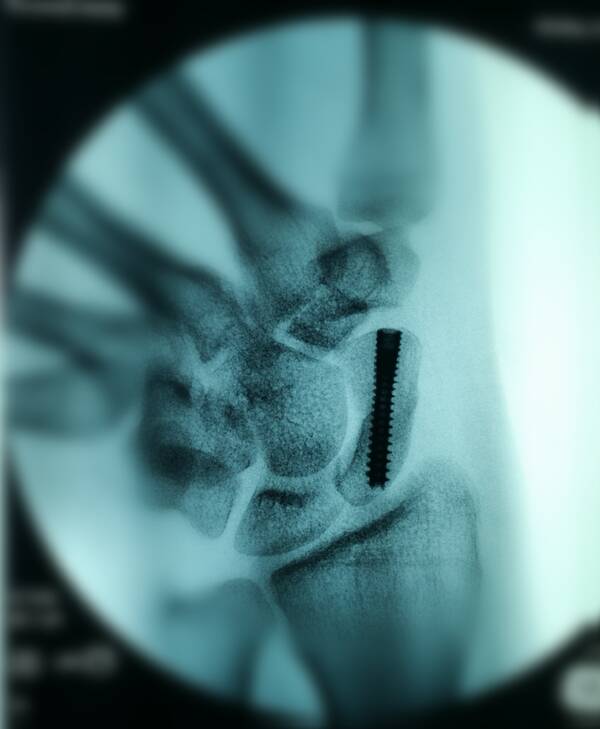

舟骨骨折内固定

关节镜下打磨植骨

治疗陈旧性舟骨骨折

四个位置均在中心

才可以打钉